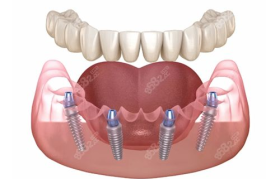

满口种植牙作为一种全面的牙齿修复方案,能够为缺牙患者提供接近自然牙齿的咀嚼功能和美观效果。许多人在考...